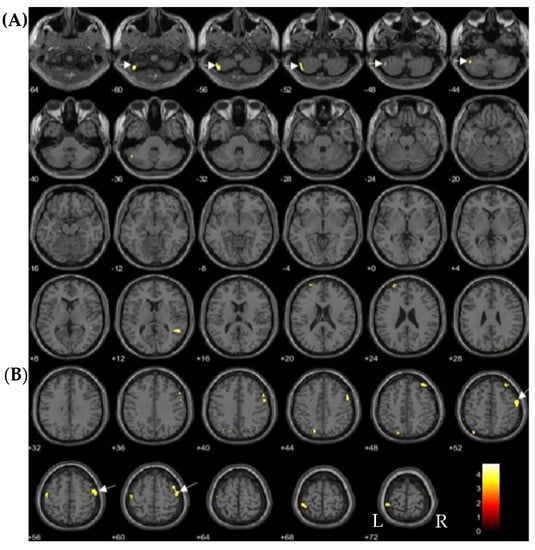

| Inverse correlations | ||||||

| TCDD | Anterior temporal cortex | 905 | ||||

| (Left medial temporal pole) | 3.81 | −41 | 20 | −38 | ||

| (Left fusiform gyrus) | 3.90 | −27 | 8 | −47 | ||

| TEQ-PCDDs | Left medial temporal pole | 333 | 3.63 | −39 | 21 | −38 |

| Positive correlations | ||||||

| 1,2,3,4,7,8-HxCDD | Left cerebellum lobule VII | 373 | 3.87 | −42 | −60 | −57 |

| Right middle frontal gyrus | 505 | 3.86 | 41 | 6 | 60 | |